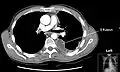

Chest computed tomography is more accurate for diagnosis and may be obtained to better characterize the presence, size, and characteristics of a pleural effusion. Lung ultrasound, nearly as accurate as CT and more accurate than chest X-ray, is increasingly being used at the point of care to diagnose pleural effusions, with the advantage that it is a safe, dynamic, and repeatable imaging modality.[15] To increase diagnostic accuracy of detection of pleural effusion sonographically, markers such as boomerang and VIP signs can be utilized.[16]

Massive left-sided pleural effusion (whiteness) in a patient presenting with lung cancer.